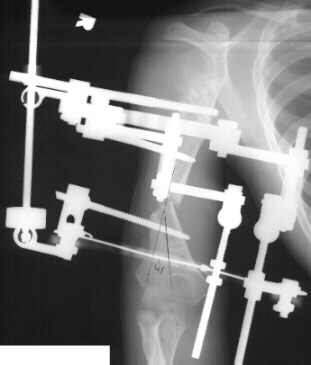

At the age of 11 years 6 months the patient underwent corticotomy, application of Ilizarov's external fixator and angular correction of right humerus. A 5 mm EBI half-pin was placed in the proximal humerus laterally. Lateral incision was placed over the distal humerus to identify the radial nerve; a small incision was placed through the brachialis muscle down to the humerus at the apex of the deformity for corticotomy. A significant amount of malrotation, approximately 100 of the 150 degrees malrotation, was corrected by internally rotating the distal fragment. A 1.8 mm Olive wire was drilled medial -to-lateral across the distal fragment just above the olecranon fossa. The frame was modified for 5/8`` ring with the open aspect anteriorly. It was placed across the Olive wire and the arch was placed posterolaterally. The angular correction devices were placed medially, and the lengthener was placed laterally. An additional 5 mm half - pin was placed posteriorly to the transfixion pin distally through the distal humerus.

Lengthening started 7 days after the corticotomy with rate of 1 mm / day. Nine weeks after the corticotomy there was good bone healing with 4 cm gap of new bone. A 30 degree of flexion contracture of the right elbow developed. Hardware was removed and good new bone was noted .